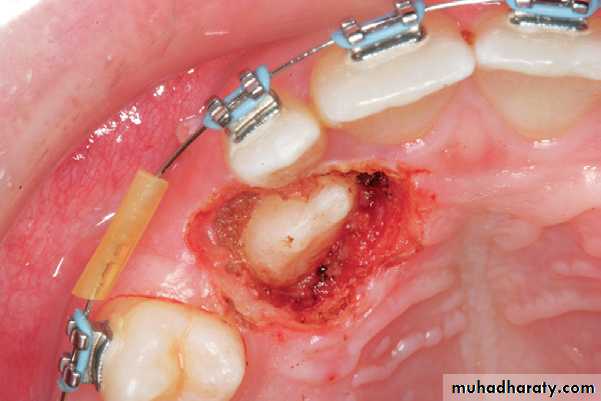

PALATALLY IMPACTED CANINES

The treatment options for the palatally impacted canine include open or closed eruption techniques.After removal of the deciduous teeth, a palatal flap is created, underneath which part of the bone covering the teeth is exposed. A round bur is then used to remove the bone covering the crowns and orthodontic brackets are placed for traction of the teeth into their normal position in the dental arch. The area is then irrigated with saline solution and the flap is closed with interrupted sutures.

Radiograph showing impacted maxillary canines with a palatal localization

Clinical photograph of the area of impaction

Palatal incision along the cervical lines of teeth using a scalpel with a no. 15 blade

Reflection of the mucoperiosteal flap. Arrow points to the nasopalatine nerve

Removal of the bone covering the crowns of impacted teeth

Surgical field immediately after exposure of

impacted teeth. Orthodontic brackets have been placed on exposed parts of the crowns of the teethSurgical field after suturing